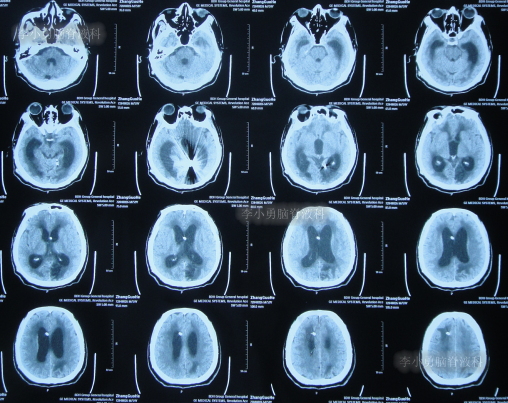

患者于2022年3月16日早晨起床后,无诱因突发头痛,恶心及呕吐,嗜睡,急就诊于当地黑龙江省海伦市某医院,查头颅CT扫描脑出血(片子丢失),因技术有限,120急救车转至上级的黑龙江省哈尔滨某三甲医院,再次复查头颅CT示出血量无明显增多(片子丢失),当天给予脑室外引流术,脑室外引流术后次日查头颅CT示脑出血脑室引流术后(图-1),医生考虑为动脉瘤出血。

图-1:2022年3月17日头颅CT